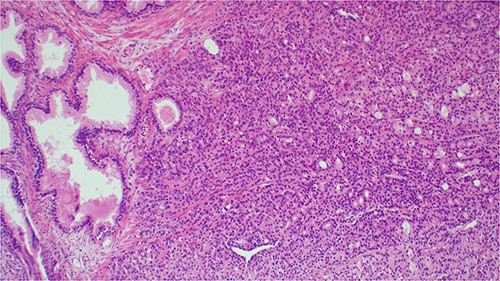

On physical examination, the patient was afebrile, not pale, not jaundiced, and not cyanosed. Per abdomen, there were normal abdominal contours that moved with respiration; no organomegally was appreciated. On digital rectal examination (DRE), the patient had a normal anal verge with a normal anal sphincter tone and a hard, grade 3 nodulated prostate. The median sulcus was not obliterated. His vital signs were within normal limits. His laboratory test results revealed an elevated prostatic specific antigen (PSA) of 58.3 ng/mL (0.01–4.00) and a low hemoglobin of 9.4 g/dL (12–15). A cystoscopy results were normal. A clinical impression of prostate cancer was entertained. The patient underwent transurethral resection of the prostate (TURP) to treat symptoms of an enlarged prostate as well as histopathology. The biopsy results confirmed the diagnosis of invasive prostatic adenoma carcinoma; Gleason score 3 + 4 = 7 (Fig. 1).

Histopathology image showing invasive prostatic adenocarcinoma, hematoxylin and eosin staining (H&E) staining 100× original magnification.